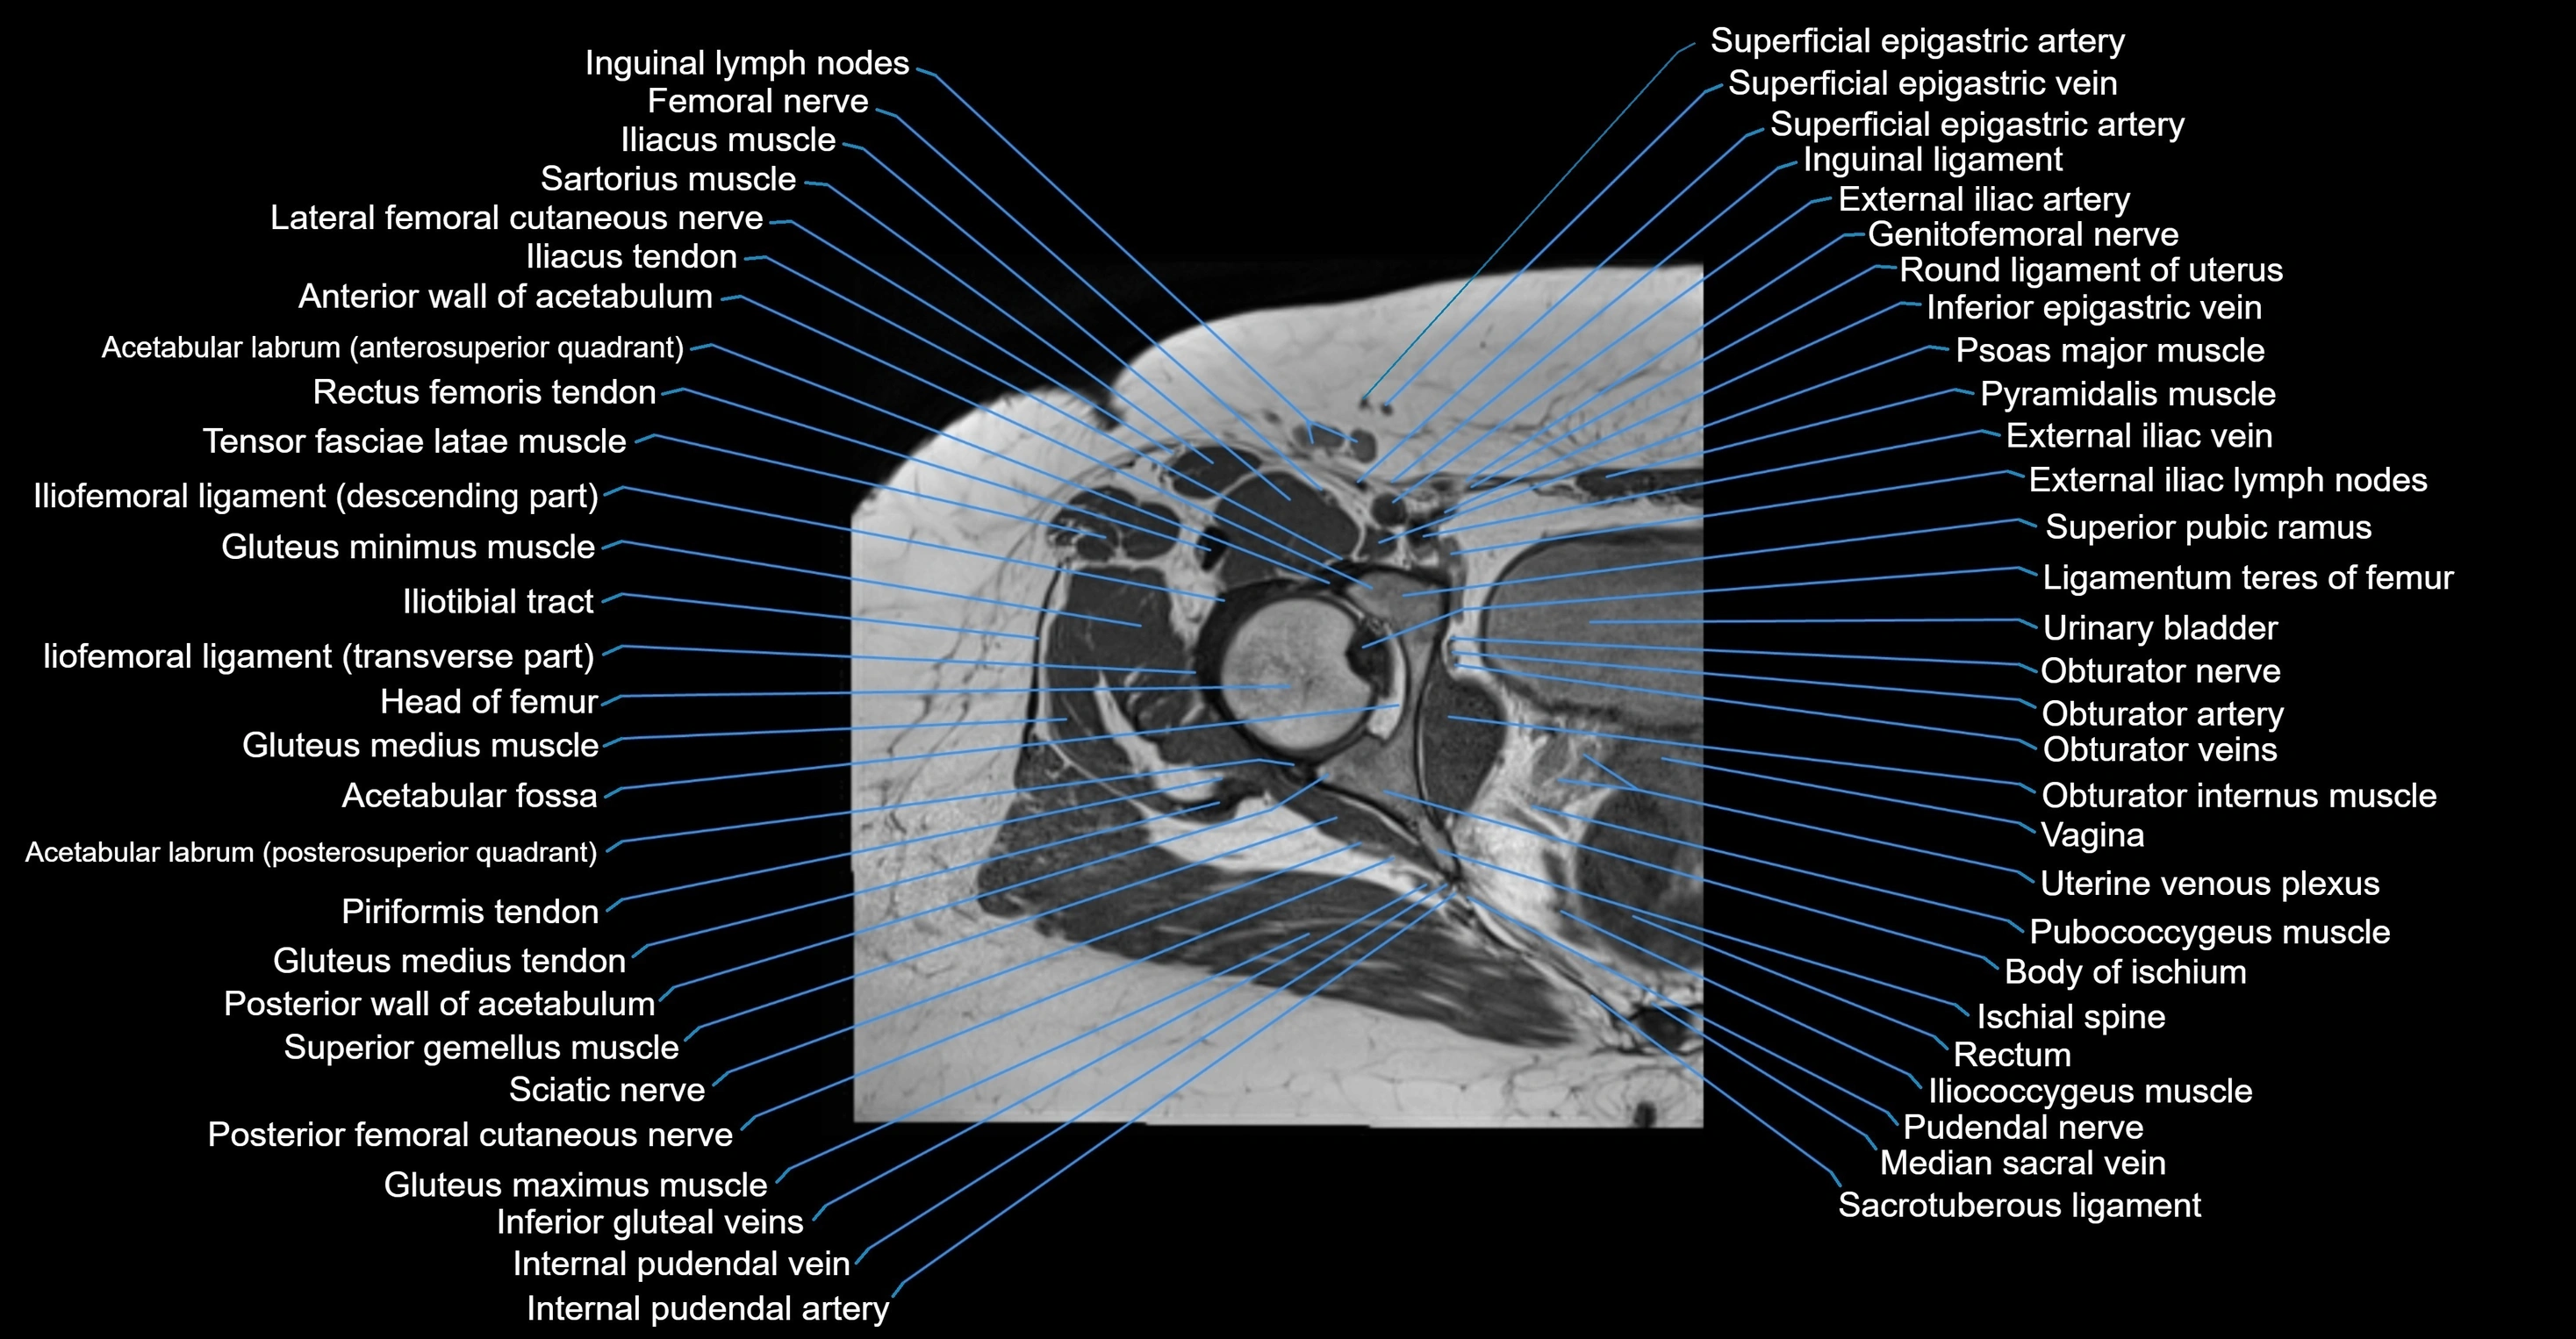

- Acetabular labrum

- Acetabulum

- Anterior wall of acetabulum

- Body of ischium

- External iliac artery

- External iliac vein

- Femoral nerve

- Head of femur

- Iliococcygeus muscle

- Iliopsoas muscle

- Ilium bone

- Inguinal ligament

- Inguinal lymph nodes

- Ischial spine

- Ligamentum teres (ligament of the head of femur)

- Median sacral vein

- Obturator internus muscle

- Obturator nerve

- Obturator vein

- Obturator veins

- Psoas major muscle

- Pubococcygeus muscle

- Pudendal nerve

- Pyramidal muscle (pyramidalis muscle)

- Rectum

- Round ligament of uterus

- Sacrotuberous ligament

- Superior pubic ramus

- Tensor fasciae latae muscle

- Urinary bladder

- Uterine venous plexus

- Vagina